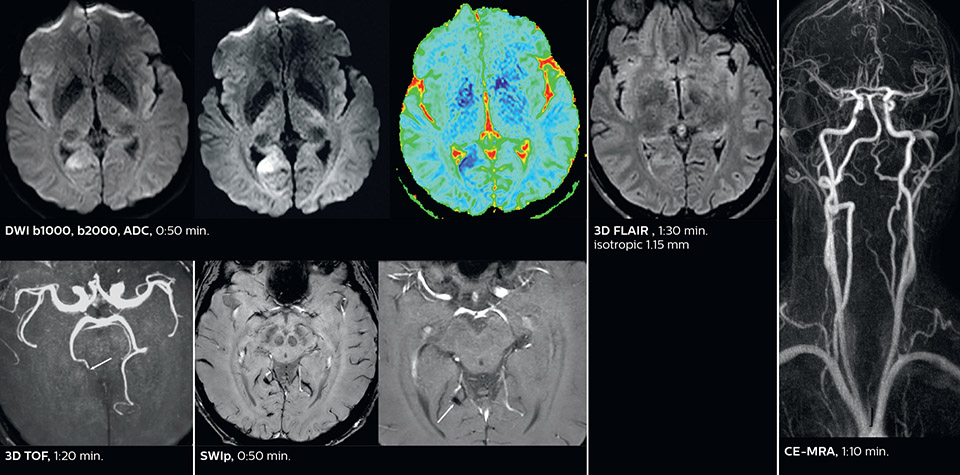

Comprehensive stroke MRI within acceptable time

Dr. Savatovsky appreciates the improvements and flexibility that Elition with Compressed SENSE and MultiBand SENSE provides, particularly for stroke patients. “For stroke, it allows us to cut about 5 minutes off of our stroke protocol, or to keep the same acquisition time and get more insights.”

The ability to perform more sequences can help in making a swift and confident diagnosis. “For example, our stroke cases usually include the regular sequences that every center does (b1000 diffusion, FLAIR, time-of-flight angiography), but we also image supra aortic vessels, and we can replace a gradient echo sequence with a fast 50-second susceptibility-weighted sequence, and all of this doesn’t add much time. because all the regular sequences are accelerated on Elition.”

“The time savings with Compressed SENSE and MultiBand SENSE make it easier to add sequences to give us additional insights. Depending on the context and the first results, we might add a DSC perfusion to assess the ischemic penumbra, an ASL perfusion to help find an alternative cause in case of normal diffusion, or add a high-resolution T1 sequence for a stroke patient, to quickly assess wall imaging in emergency cases. The additional sequences can help improve patient management, because we can already consider some alternative diagnoses if the morphological MRI is normal.”

Fast acute stroke protocol

This is an example of acute ischemic stroke with distal occlusion of the right posterior cerebral artery. Note the improved visibility of the ischemic territory on the diffusion weighted image with high b-value. The 3D FLAIR shows a distal PCA occlusion. The fast SWIp depicts the thrombus on the isolated second echo image. The total scan time (including SmartBrain, preparations and a fast 3D T1w TSE Gd) is 8:00 minutes.